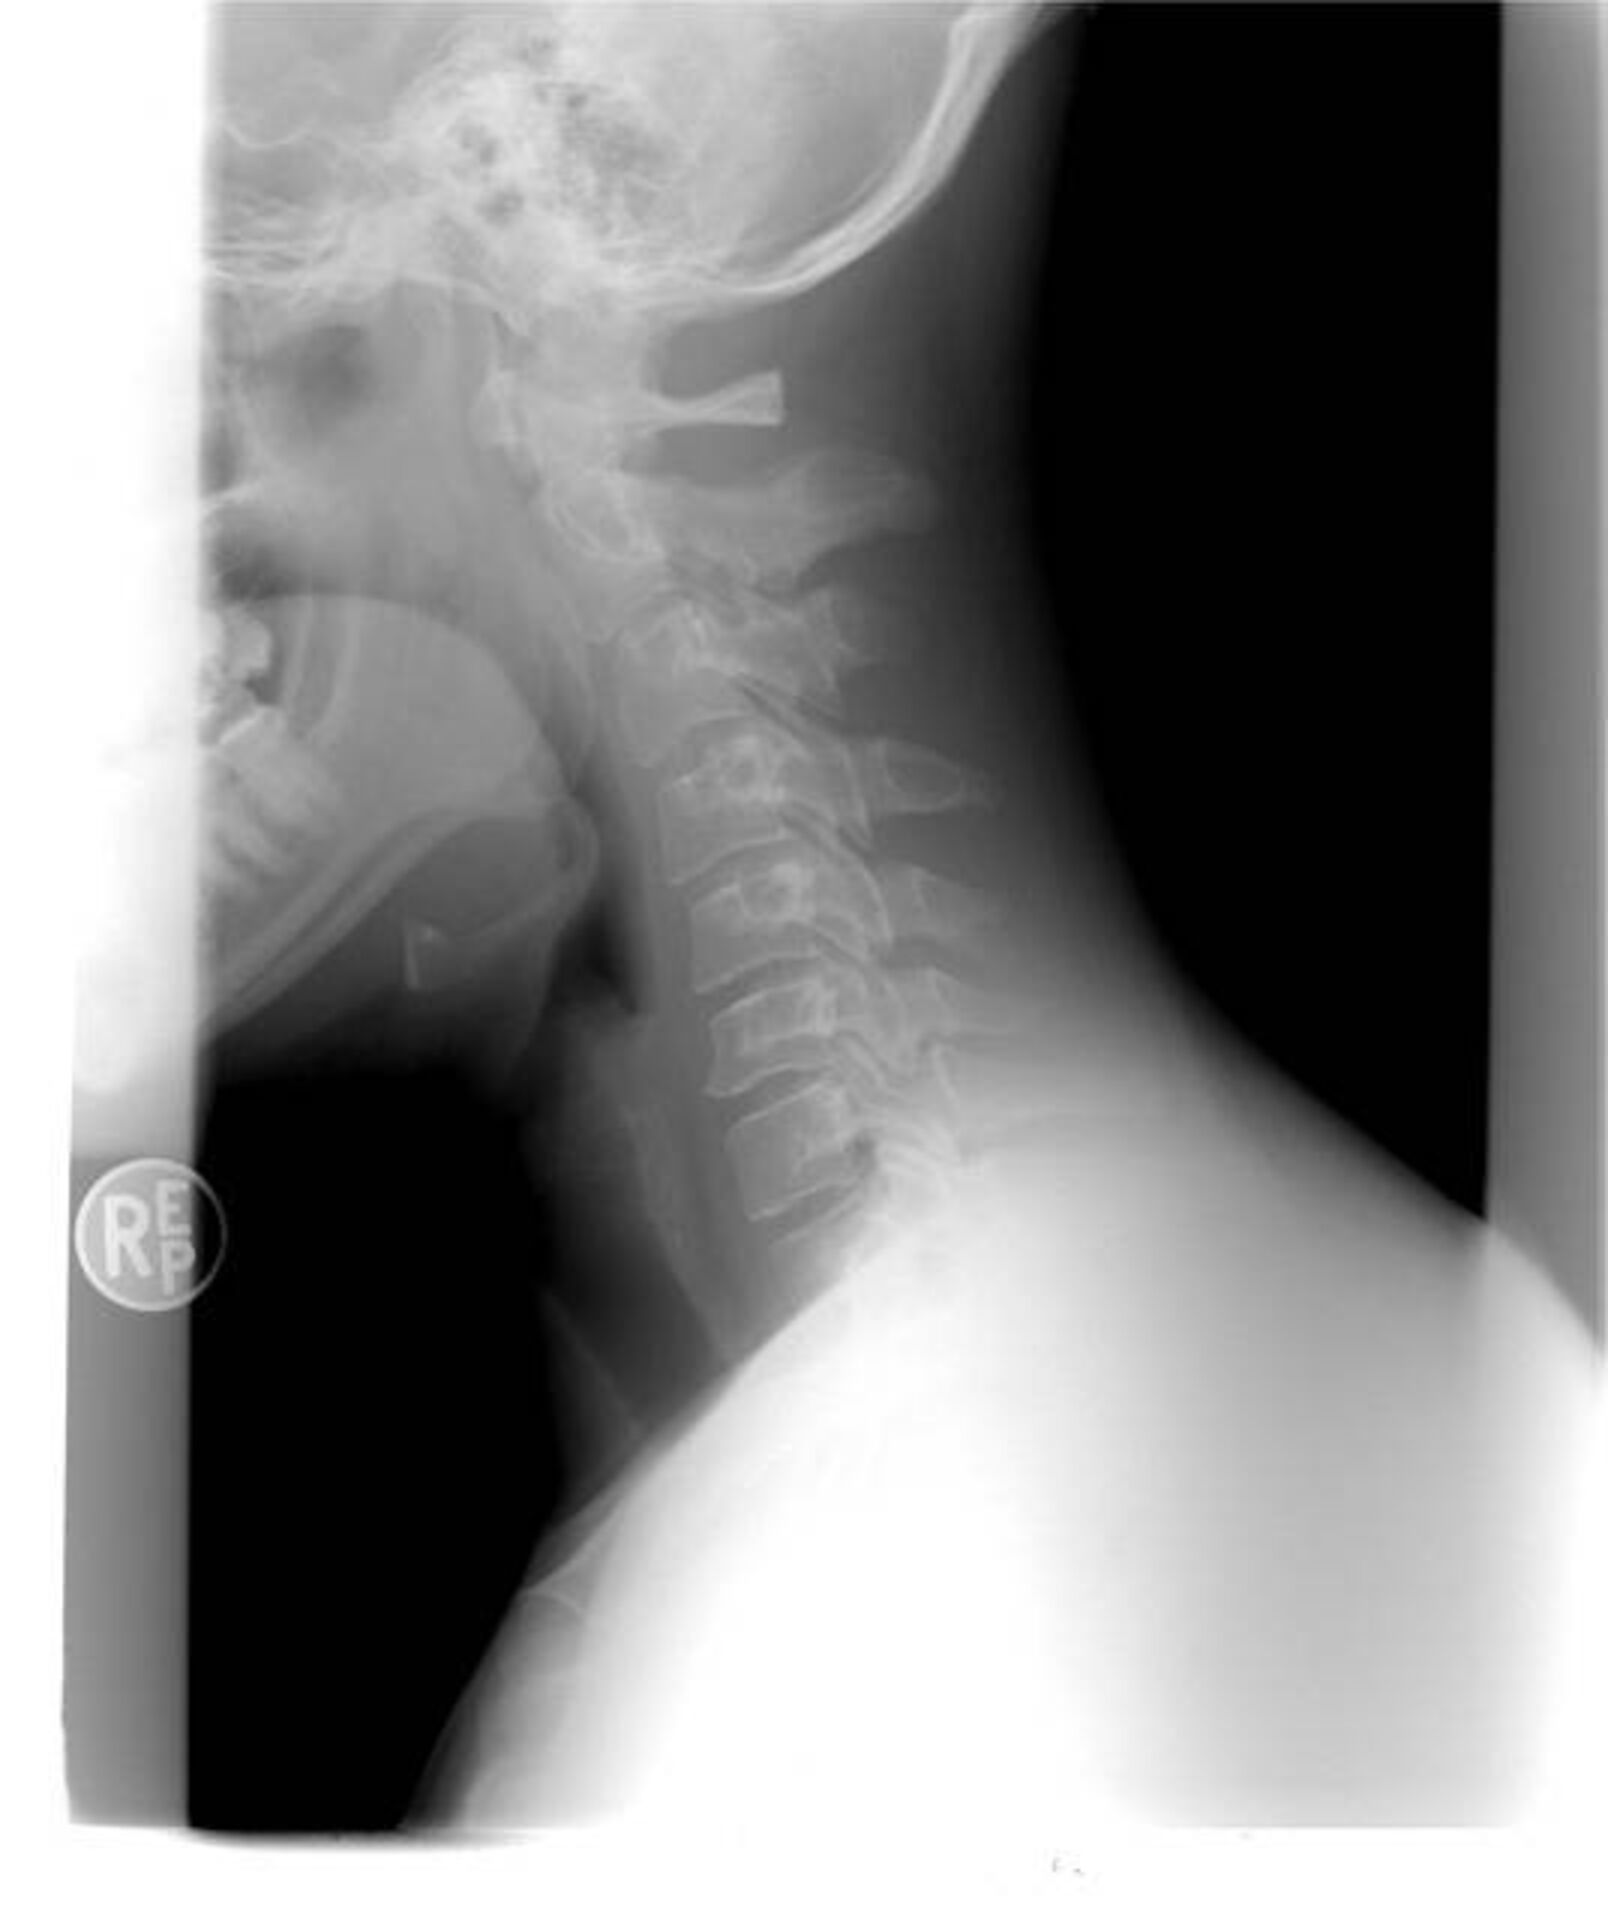

Comment faire valoir ses droits après un accident de la route avec traumatisme cervical dans le secteur d’Aubagne La Ciotat ?

Après un accident de la route avec traumatisme cervical, souvent appelé « coup du lapin », la reconnaissance de vos droits et l’obtention d’une indemnisation accident de la route adaptée impliquent plusieurs démarches clés, particulièrement si vous êtes victime dans le secteur d’Aubagne, La Ciotat...